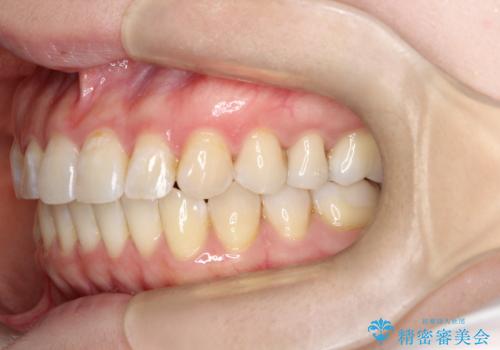

【インビザライン 】前歯の凸凹をなおしたい

- 前歯の凸凹を主訴に来院されました。

インビザライン にて治療を行い、歯並びが綺麗になったと満足していただきました。

前歯のガタガタの量が多かったため、IPR(歯のサイズを小さくするための処置)を行なって治療しました。